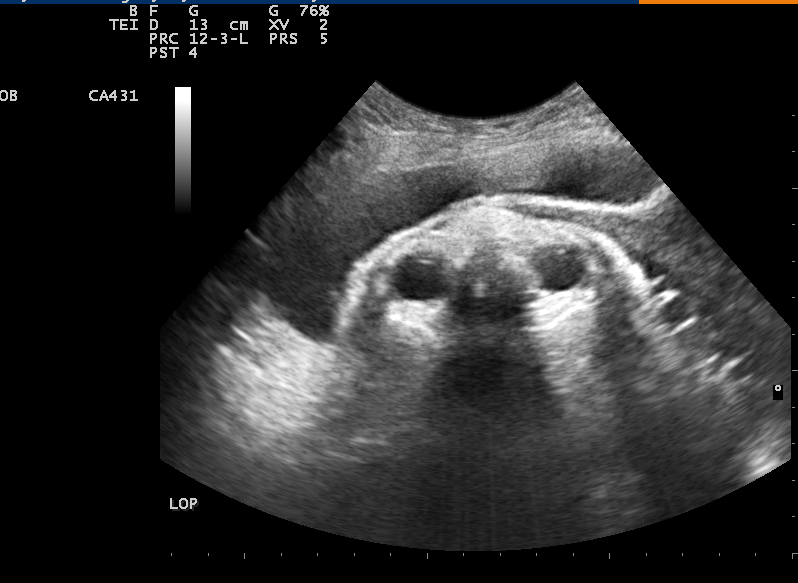

经腹产程超声在左侧锁骨中线横切

观察到双眼球征象为左枕后胎方位

经产程超声监测,发现胎位为枕后位,立即进行系列性的自由体位转胎位(俯卧位、膝胸卧位等),宫缩间歇时,轻摇摆髋部等导乐分娩,加上产妇积极配合,医生、助产士密切观察胎头下降及胎心变化情况,经过5次的体位纠正,在产程超声的监测下,廖女士成功地转胎位为枕左前位,最终顺利分娩。

产程超声:采用超声检测宫颈扩张程度、胎头下降、胎方位等,选择合适的分娩方式,最大程度减少母儿并发症的发生。